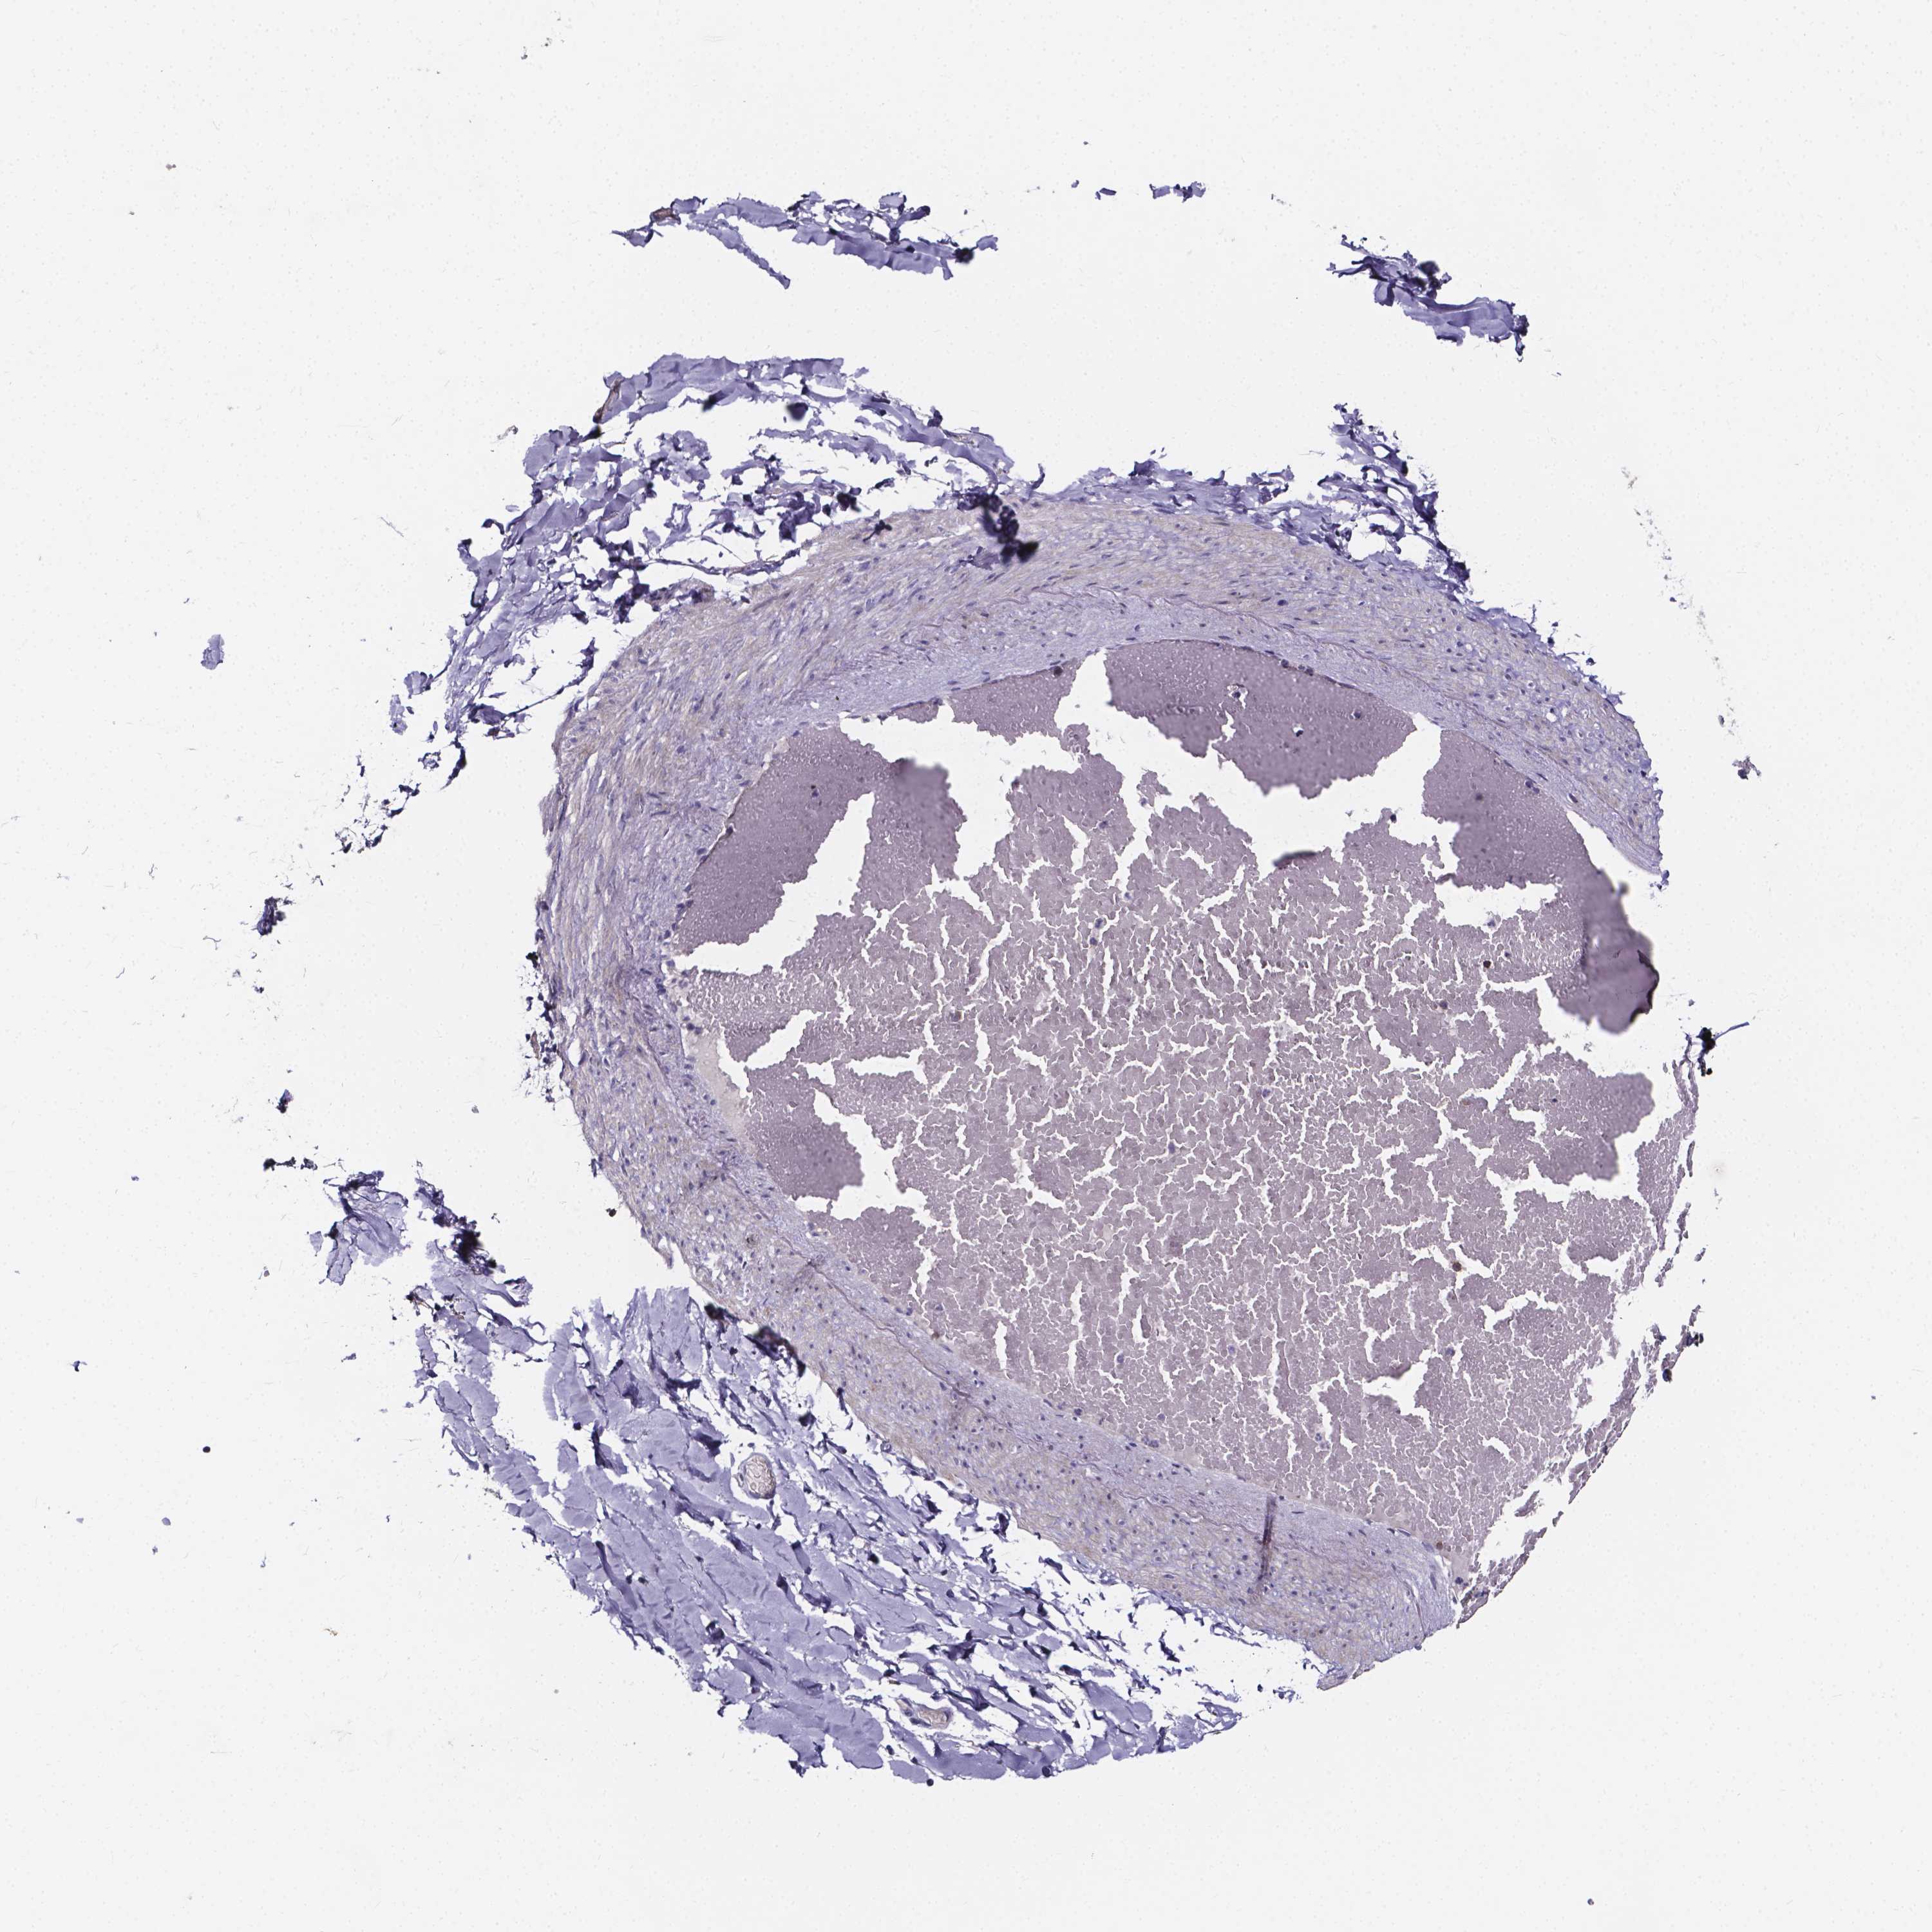

SOFT TISSUE 2 - Antibody stainingi

Antibody staining in the annotated cell types in the current human tissue is reported as not detected, low, medium, or high, based on conventional immunohistochemistry profiling in selected tissues. This score is based on the combination of the staining intensity and fraction of stained cells.

Each image is clickable and will lead to virtual microscopy that enables deeper exploration of all samples and also displays staining intensity scores, fraction scores and subcellular localization as well as patient and tissue information for each sample.

Antibody HPA031422Antibody HPA031425

Fibroblasts Not detectedNot detected

Peripheral nerve Not detectedNot detected